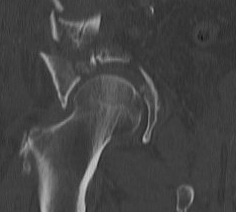

X-ray / 5 standard views

AP / Six X-ray Landmarks

1. Iliopectineal line

- along pelvic brim to pubic symphysis

- anterior column

2. Ilioischial Line

- pelvic brim to ischial tuberosity

- posterior column

- formed by posterior 4/5 of quadrilateral surface ilium

3. The Teardrop

- lateral: subchondral bone condensation at anterior margin of cotyloid fossa

- medial: anterior flat part of quadrilateral surface of iliac bone

4. Roof of acetabulum

5. Anterior rim of acetabulum

- semilunar

6. Post rim of acetabulum

Judet views / 45o obliques

Internal Oblique / Obturator Oblique

- affected side rotated forward

- anterior column + posterior wall

External Oblique / Iliac Oblique

- unaffected side rotated forward

- posterior column + anterior wall